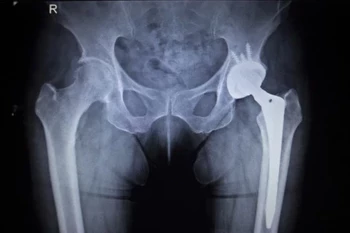

There have been several protocols (guidelines/recommendations) published with respect to antibiotic prophylaxis in dentistry. These protocols concerned mainly cardiac patients who are under the risk of developing bacterial endocarditis as well as those with prosthetic joints. The recommendations dealt with the doses and intervals of antibiotic prophylaxis, who requires such prophylaxis and which dental procedures …